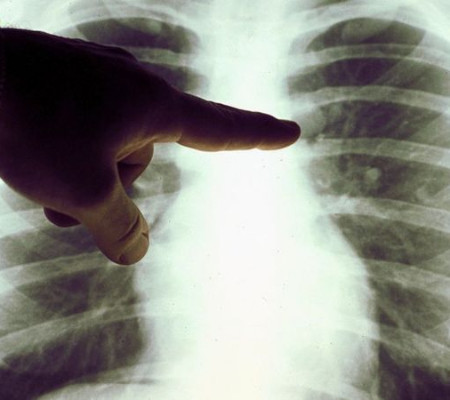

Caso de linfoma | Foto: Reprodução

Sem medicação específica adicional, linfoma de paciente que contraiu a Covid-19 desaparece (Foto: Getty Images)